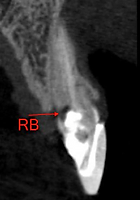

Paciente nos procurou com queixa estética pelo tratamento com facetas em porcelana nos incisivos centrais. Após avaliação clínica e dos exames radiográficos foi verificada reabsorção interna no incisivo central superior direito, condenando esse dente à exodontia.

Realizamos então a exodontia do incisivo central superior direito, seguido de implante, enxerto 100% com biomaterial, provisório imediato e posterior troca da faceta do incisivo central superior esquerdo. A maior preocupação era utilizar uma técnica cirúrgica que mantivesse o alinhamento da gengiva com os dentes vizinhos e uma reabilitação protética que escondesse o implante e a faceta do dente vizinho no conjunto do sorriso.